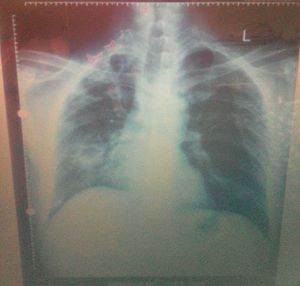

Diagnosis????

Right sided middle zone consolidation?

1. Right sided diaphragm paralysis 2. Sub diaphragmatic abscess 3. Massive hepatomegaly

No its a pulmonary case!!!

Pneumothorax???